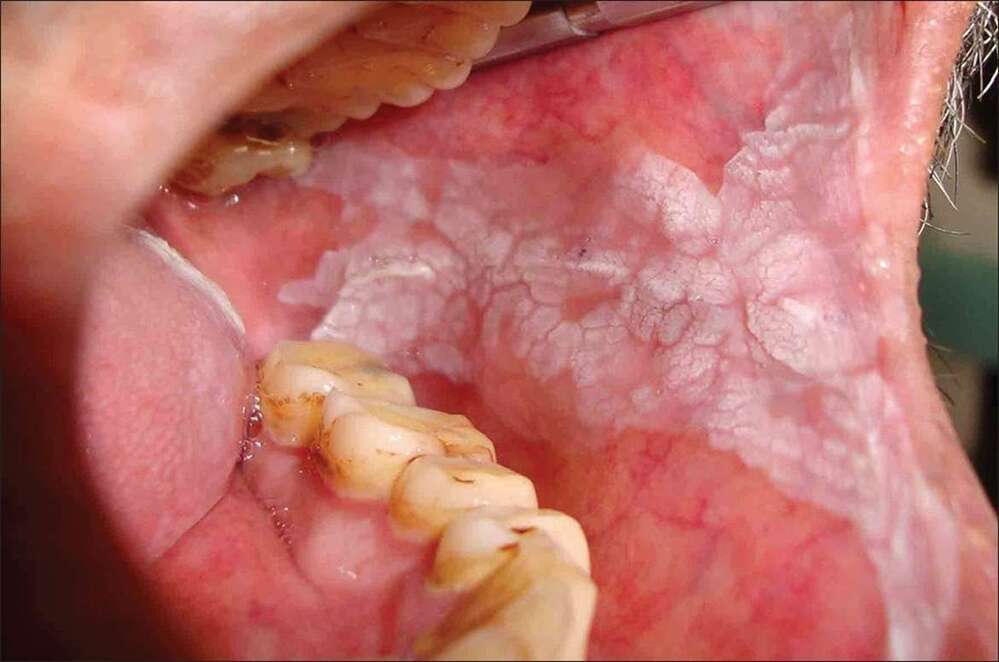

口中出現無法清除的白斑嗎?高雄市民生醫院牙科醫師陳晶晶指出,口腔白斑症是口腔內無法刮除的白色病變,顏色以白色為主,有些會略帶紅色或是紅白相間,由於大部分患者不會有特別的感覺,所以在病症初期最容易被忽略,有些患者會感覺斑塊處黏膜部位有粗糙,甚至輕微疼痛後才會就醫,其實口腔白斑症與口腔癌關係密切,患者切勿掉以輕心。

陳晶晶表示,未消失的白斑若切片檢查顯示沒有其他變化,可用光動力治療、冷凍治療、二氧化碳雷射切除,病症約二至四周就會復原。但若白斑症已有上皮發育異常或疣狀增生時,則建議將病灶整個切除,再施以植皮手術。一般的口腔白斑約有10% 可能將來會惡化成為口腔癌,若已伴隨有疣狀增生、上皮發育異常的口腔白斑,日後發生口腔癌的機會更大。